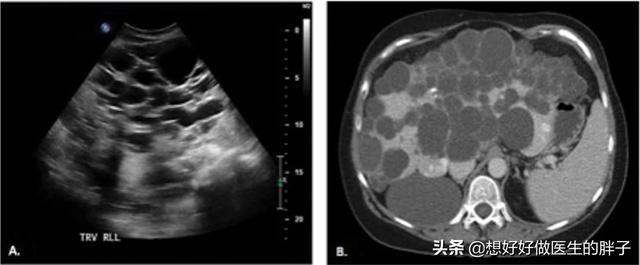

另外还有一种问题也是比较棘手的,那就是多囊肝,多囊肾。这是一种先天性的疾病,往往症状随着年龄的增长越来越重,而且随着病情的进展有可能发生肝衰竭或者是肾脏衰竭,因为形成的囊肿过多过大严重的影响了肝脏和肾脏的功能(下图为多囊肝)。

多囊肝